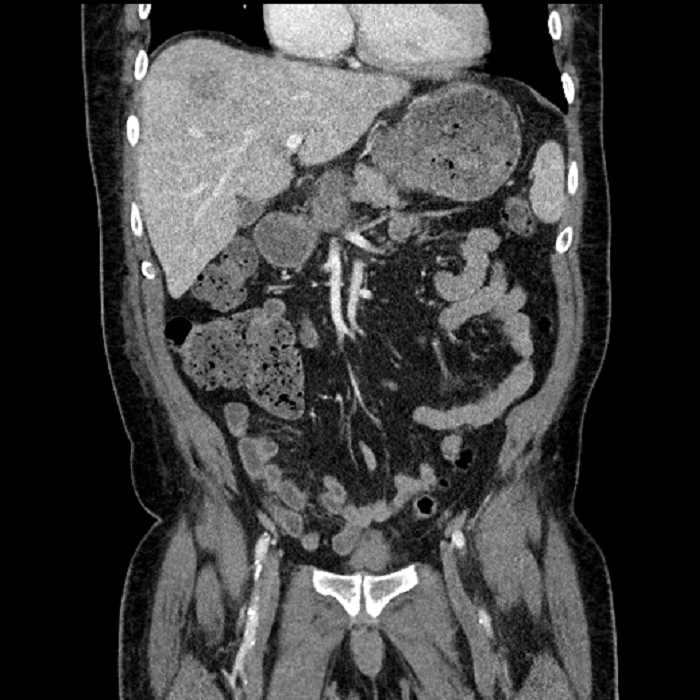

• Large fluid density structure in hepatic segments 7 and 8 measuring 10 x 7 x 7 cm with internal septation and circumferential ill-defined low density compatible with edema

• Peripherally enhancing subcapsular collections along the anterior margin of the left hepatic lobe measuring 3 x 1 cm and 2 x 1 cm

• Hepatic abscess

Acute sigmoid diverticulitis complicated by a small contained perforation and a large abscess in the right hepatic lobe. Additional small subcapsular abscesses along the anterior margin of the left hepatic lobe.

Additionally, loss of the normal fat plane between the peridiverticular collection and adjacent thickened loops of small bowel raises the potential for an enterocolonic fistula.

Hepatic abscess showing the double target sign with low density internally surrounded by a thin inner enhancing rim (red arrow) and ill-defined outer low density rim (yellow arrow). Blue arrow indicates an internal septation. Red arrows: additional smaller subcapsular abscesses. Red arrow: focal contained perforation associated with diverticulitis.